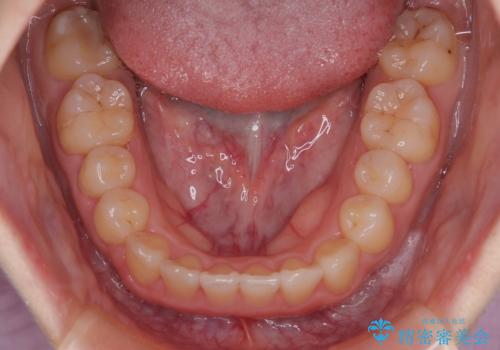

- 前歯の叢生を主訴に来院されました。目立たない装置を希望されたためインビザラインで治療を行いました。

IPRと拡大をし、叢生を治しました。右上2番は反対咬合でしたが短期間できれいに治りました。